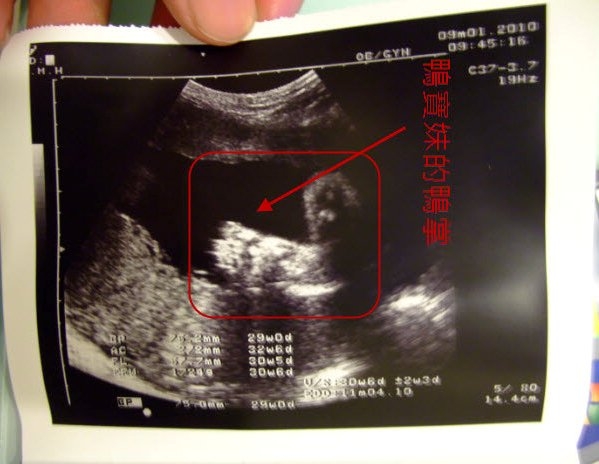

31週,1700G。

醫生說我羊水很多,所以李千金的五官可以看的滿清楚的,

很明顯的李千金有我和鴨寶的肉鼻,小孩果真不能偷生!!